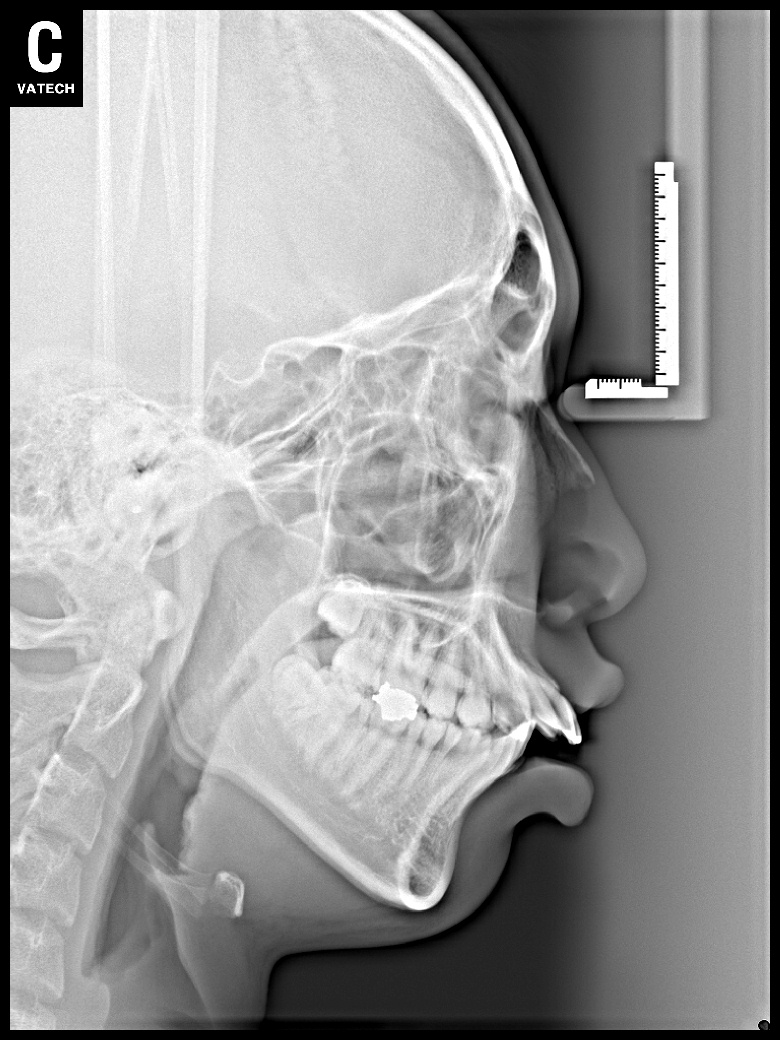

치료 전 사진입니다.